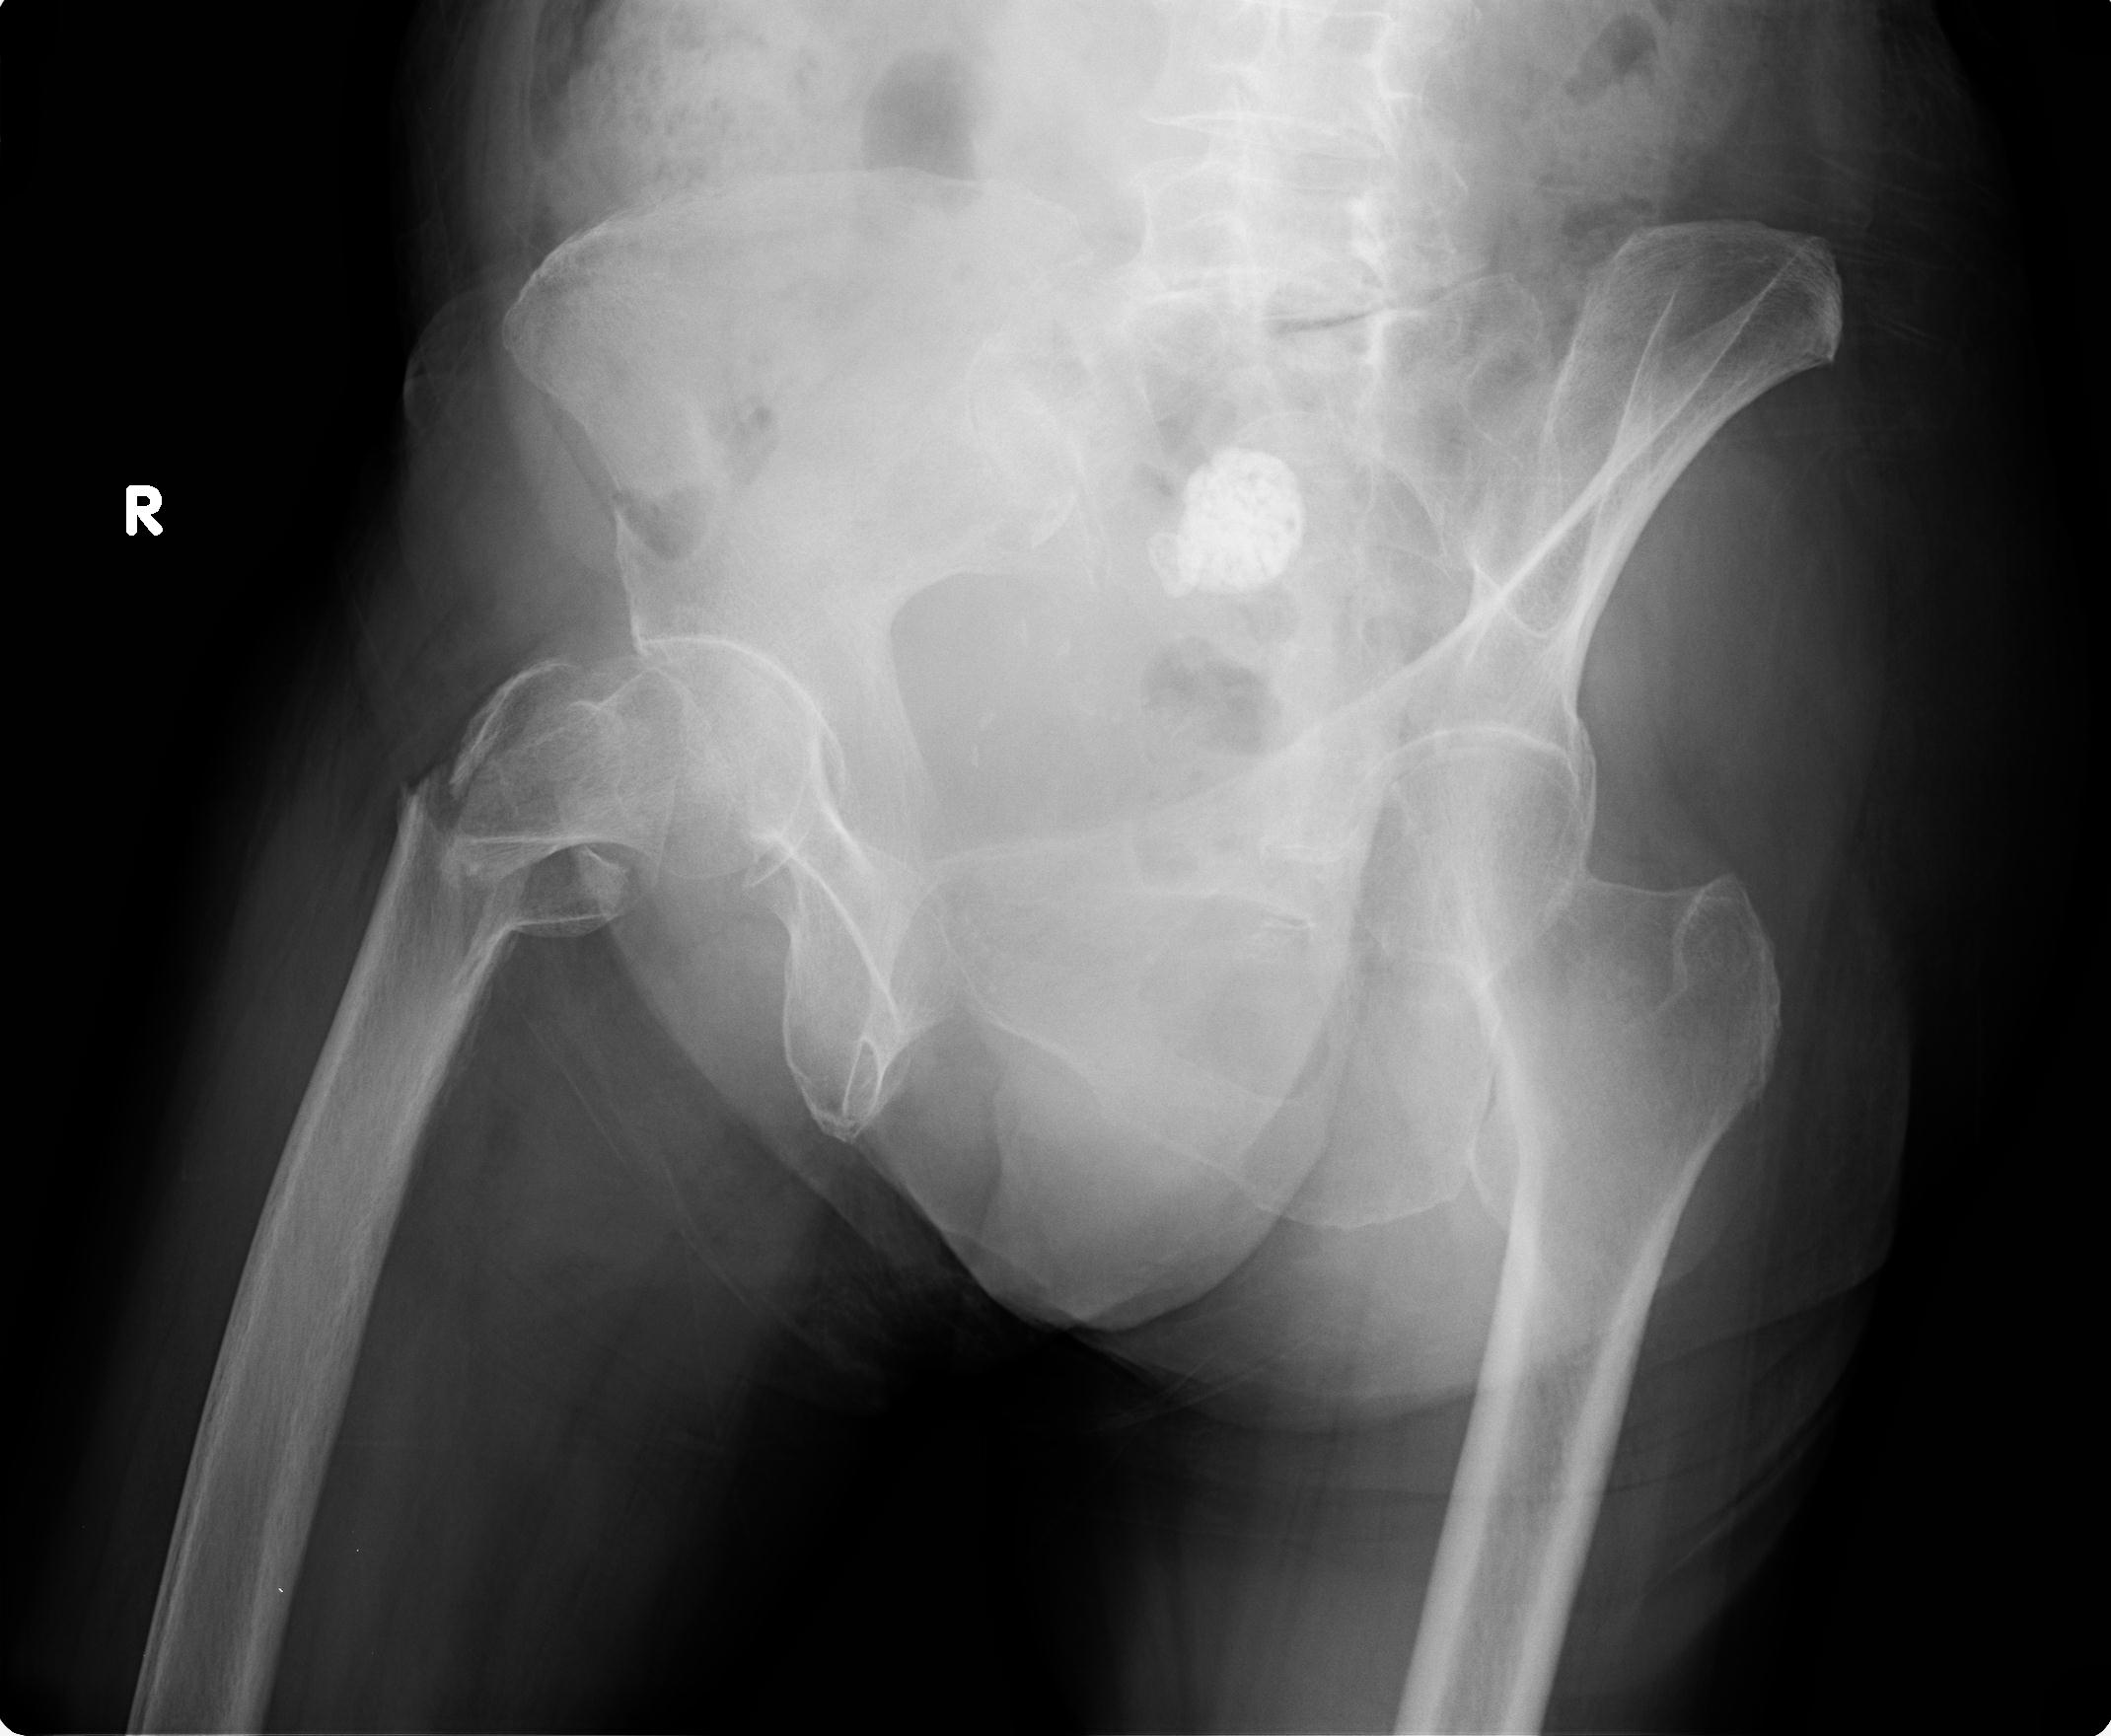

100703 1/27 両股正面+軸 1/29 両股正面+軸 94歳女性 パンソンロン